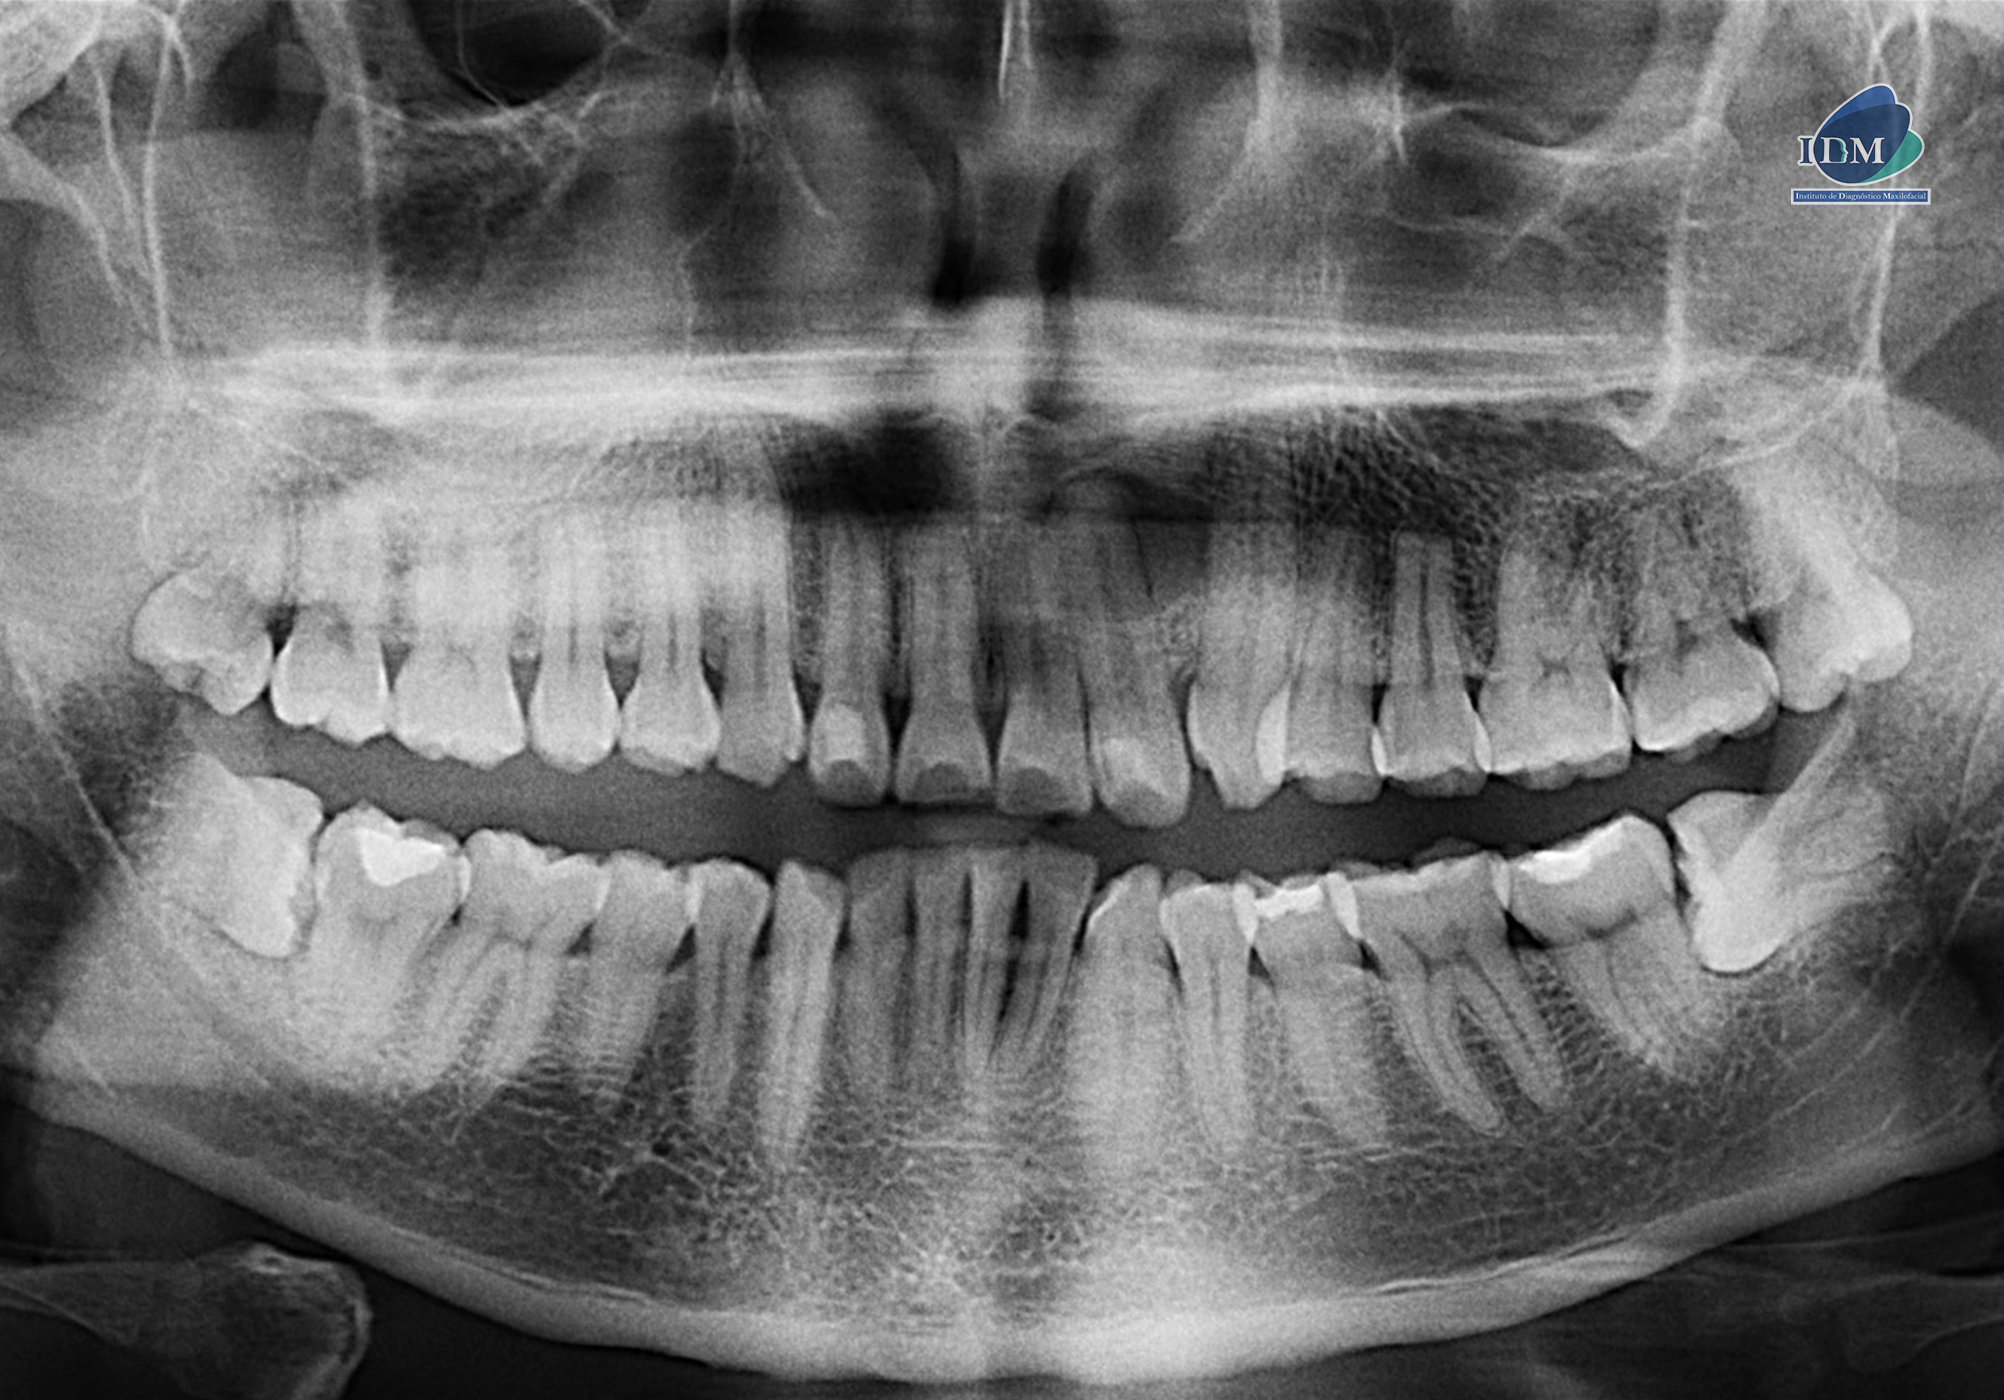

Radiografia Panorámica

Paciente masculino de 33 años acude para una revisión general. A la evaluación de la radiografía panorámica se observa la neumatización de ambos senos maxilares, múltiples restauraciones y piezas 38 y 48 impactadas en posición horizontal. Asimismo, se observa la pieza 22 con material restaurador en cara libre y una imagen radiolucida corticalizada de forma redondeada que se proyecta sobre la porción radicular de la misma que se extiende hasta mesial de la pieza 23.